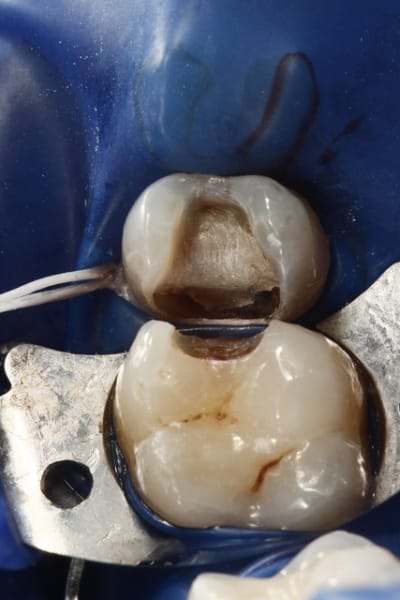

un truc que je fais souvent, quand je monte deux compo volumineux en contact, je monte le plus gros et difficile sans matrice et comme ça j'ai accès a la marge, et je peux donner une jolie forme galbée proximale

puis je monte le suivant avec une seule matrice...

plus facile je trouve d'avoir le point de contact